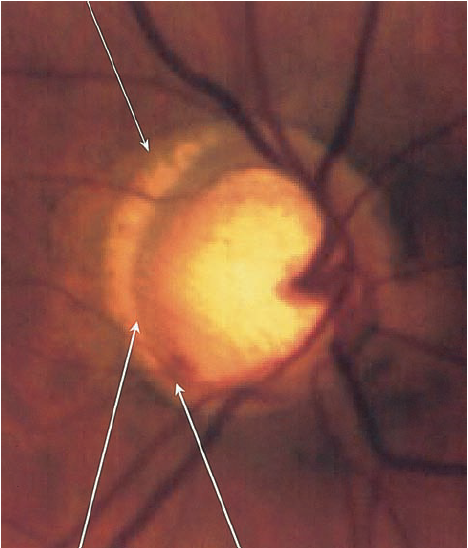

2.2. Gai thị

Tổn hại gai thị không có sự khác biệt với các loại glôcôm khác như tỉ lệ C/D lớn, tổn hại lớp viền thần kinh đĩa thị giác, thay đổi mạch máu của đĩa thị giác…Tuy nhiên, trong glôcôm nhãn áp bình thường tổn hại gai thị cũng có 1 số đặc điểm riêng:

- Lớp viền thần kinh quanh gai thị mỏng hơn so với glôcôm nhãn áp cao.

- Lõm gai không quá sâu và lớp lá sàng ít bị đấy ra phía sau hơn.

- Hay gặp tổn hại viền thần kinh gai thị khu trú ở 1 vị trí kèm theo lõm gai thị sâu và thay đổi lớp lá sàng tạo thành hố gai thị mắc phải, 75% gặp ở glôcôm nhãn áp bình thường so với 15% ở glôcôm nhãn áp cao.

BSVL1

Teo lớp sợi thần kinh quanh gai thị

Mất lớp viền thần kinh

Xuất huyết cạnh gai thị

BSVL2

Lõm gai sâu

Tổn hại gai thị(nguồn: Atlas of Glaucoma)

- Một trong những dấu hiệu thường gặp nhất trong glôcôm nhãn áp bình thường  là teo võng mạc cạnh gai thị ( vùng α và vùng β), tuy nhiên dấu hiệu này không đặc hiệu cho glôcôm nhãn áp không cao .

- Xuất huyết gai thị: rất hay gặp trong glôcôm nhãn áp bình thường.

- Tổn hại lớp sợi thần kinh quanh gai thị: hay gặp tổn hại lớp sợi thần kinh khu trú ở 1 vị trí nào đó hơn là tổn hại toàn bộ chu vi gai thị.

Tuy nhiên,  những dấu hiệu trên không đặc hiệu cho glôcôm nhãn áp bình thường , không cho phép chẩn đoán xác định mà chỉ có giá trị gợi ý glôcôm nhãn áp bình thường  mà thôi.